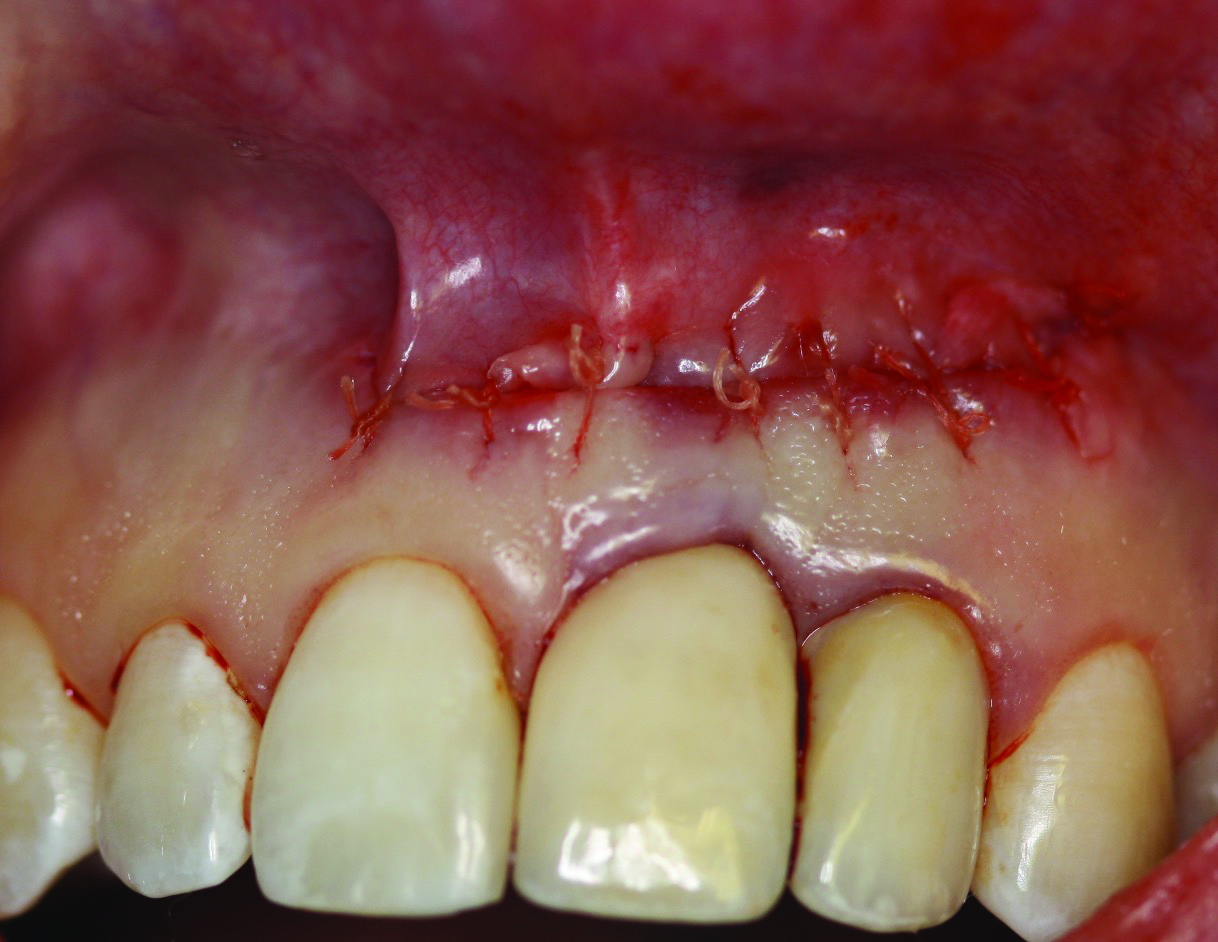

Fig 8. Case 1: Primary closure obtained using interrupted resorbable sutures.

Figure 8

In case 1, due to the high smile line and asymmetrical clinical crown lengths, the patient received a vestibular incision at the mucogingival junction with full-thickness flap elevation to access the implant apex. Implant debridement was performed with titanium curettes and brushes (Figure 5). The implant surface was treated for 2 minutes with a doxycycline–saline slurry. The peri-implant defect was grafted using particulate freeze-dried bone allograft (FDBA) (Figure 6) and covered with a collagen membrane (Figure 7). Primary flap closure was obtained using resorbable sutures (Figure 8).